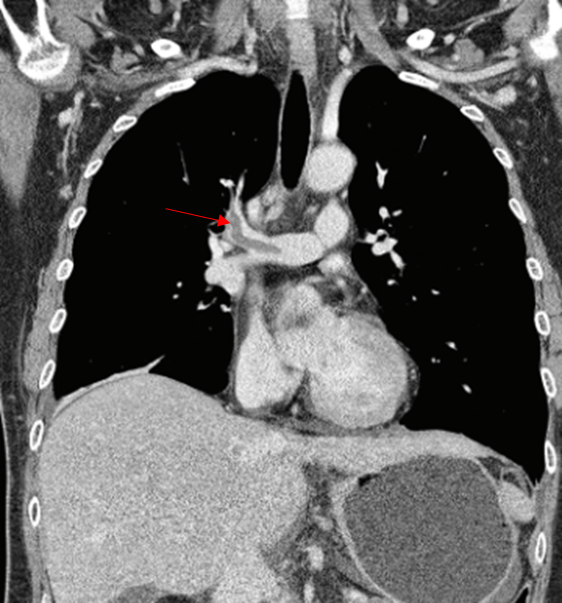

Img | CXR: 특이 소견 없음 CT: 우폐동맥 혈전 |

• 종양은 PTE의 위험인자 중 하나고, 단독으로 흉부 불편감이 있으므로 폐색전증의 가능성을 생각해볼 수 있는데, CT에서 우폐동맥 혈전이 보이므로 폐색전증으로 진단할 수 있다.